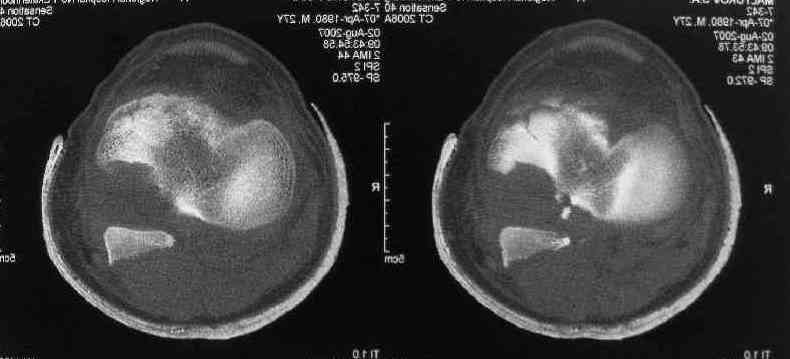

Операция из разряда травматологической "экзотики" прошла

успешно. Доступ понравился:анатомичный, хорошая визуализация, удобно

работать и оператору и ассистентам. Наложили пневможгут, но

воспользовались им только на этапе ревизии сустава. Фрагмент

развернулся на 90 град. на 2-ух "жгутах": медиально - сухожилие

m.semitendinosus, латерально - задняя крестообразная

связка. Мобилизовали,развернули и уложили на место без особого

труда. Фиксировали отмоделированной 1/3-трубчатой пластиной. Мениск

оказался неповрежден. Сустав стабилен. Обошлись без

иммобилизации, планируем начать ранние движения. Остальное на

фото, дополнительно приложены корональные срезы КТ.